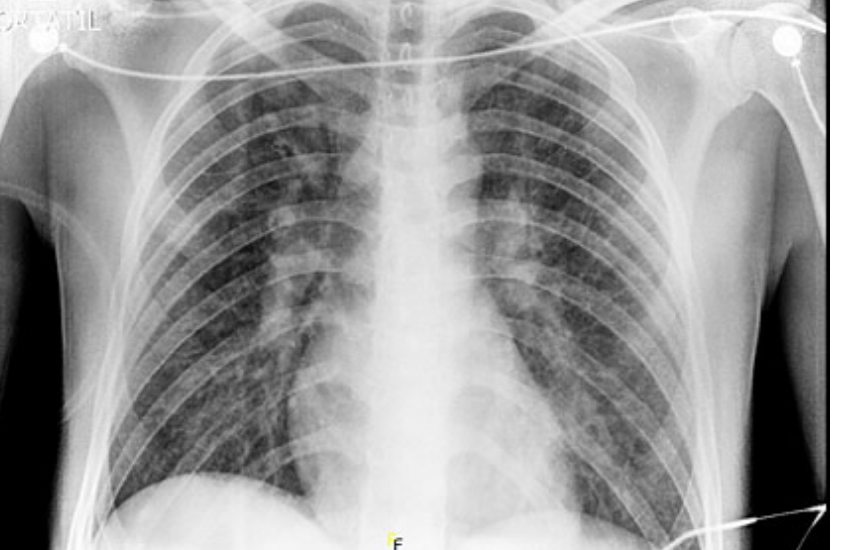

#idboardreview 25 M return from Venezuela 8d ago & 6d of F, HA, jaundice, N, V, 6 lb wtloss, dark urine. During travel walked barefoot in mud, hiked, swam, used mosquito repellent, no pre-travel medical advice. AST 14k, ALT 8k, Cr9, AP 250, Plt80, Bil7, diagnosis? #medEd #idmedEd

Viral hemorrhagic fever #YellowFever hallmarks include pathognomonic triad of hemorrhagic fever w/ jaundice & renal disease. Other viral hemorrhagic fevers may present w/ either jaundice or w/renal disease but combo suggests YF w/ appropriate exposure to mosquitoes